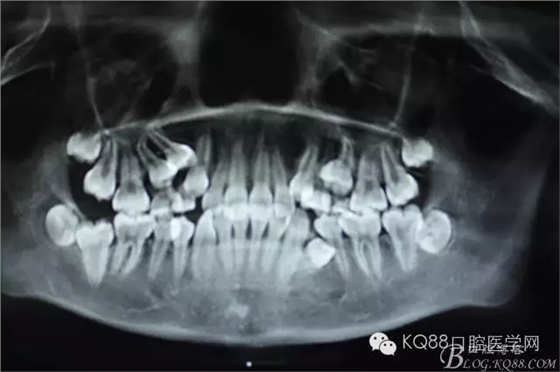

圖3.全景片檢查:14位于15與13之間,正畸科要求拔除14,難度可想而知。54、55滯留。